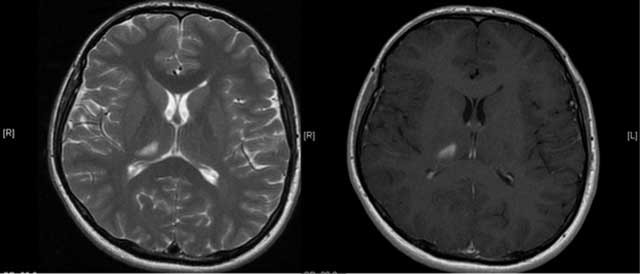

A 27-year-old male patient with an unremarkable medical history presented with acute onset of severe headache, dizziness and disequilibrium, and left sided weakness. Unenhanced CT revealed a hypodense lesion in the right thalamic and subthalamic region about 1 cm in diameter and an absent right ICA and bony carotid canal (Figure 2). On MRI, a well defined T2-hyperintense, T1-hypointense, contrast-enhancing lesion was seen in the right thalamus and subthalamic region consistent with sub-acute infarction (Figure 3). Cranial and cervical MR angiography showed right ICA agenesis and anomalous origin of the ophthalmic artery derived from right MCA. The aortic arch and major aortic branches were normal.

Figure 3

An axial T2W and enhanced T1W images show lesion consistent with subacute infarction (Case 2).